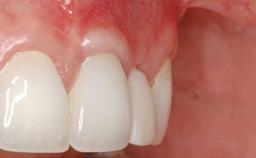

Periodontal Plastic Surgery and Prosthetic Procedures to Treat Peri-Implant Soft-Tissue Dehiscences

A 30-year-old woman was referred by her general dentist for evaluation of an esthetic complication related to previous implant treatment for congenitally missing maxillary lateral incisors. The patient’s chief complaint was the inadequate esthetic appearance of her smile. The case demonstrates the use of a combined approach to achieve optimal results. Two different flap designs - a tunnel technique and a coronally advanced flap - are employed based on the surgical objectives for the affected site.